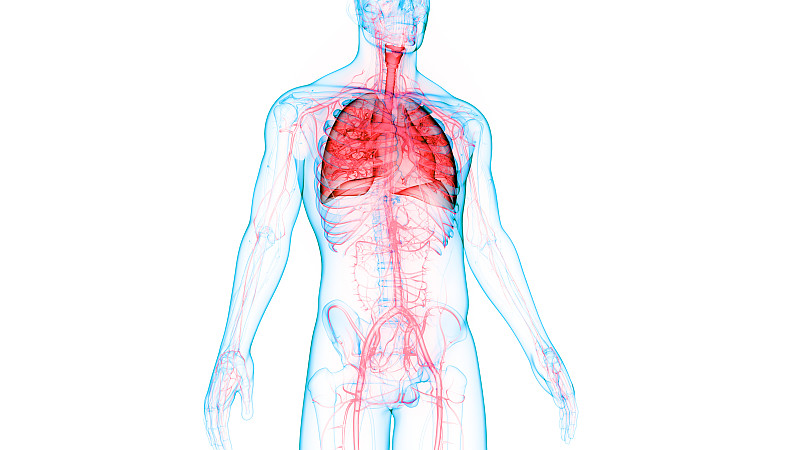

人体呼吸系统肺解剖学详情

JPG